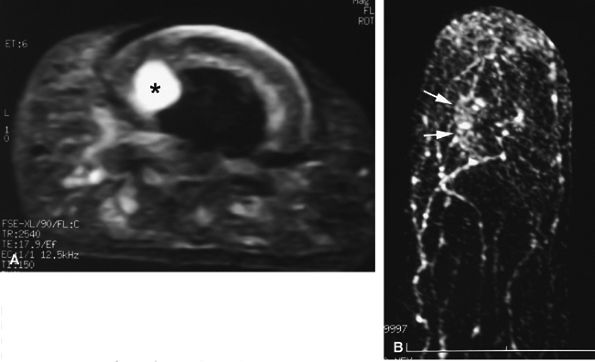

FIGURE 11.128 ● Vascular-type glomus tumor (asterisk) of the nail bed with the most common signal characteristics. (A) Axial T2-weighted image. T1-weighted images before (B) and after (C) injection of gadolinium. (D) MR angiogram. The tumor is located on the midline with an underlying bone erosion (arrowheads). The signal is high on T2-weighted images and slightly high on T1-weighted images. There is strong post-contrast enhancement on T1-weighted images and MR angiography.